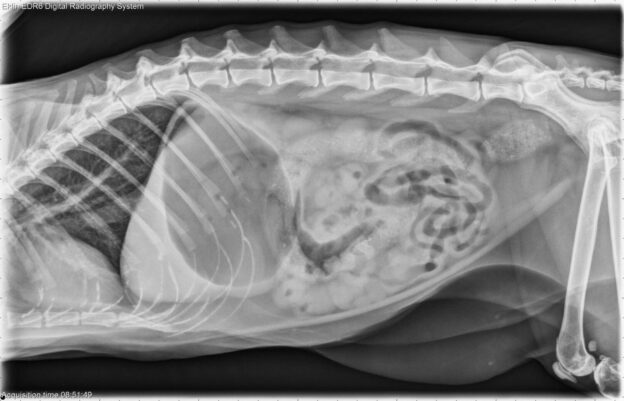

Van schaduw tot diagnose: leer kijken als een radioloog

In dit webinar uit de Klinische Cases-reeks neemt Dr. Emmelie Stock je mee door een reeks uiteenlopende radiografieën uit de dagelijkse praktijk. Stap voor stap leer je hoe je systematisch naar een beeld kijkt, subtiele afwijkingen herkent en radiografische bevindingen koppelt aan de klinische context.

Een ideale sessie om je radiologische blik te verscherpen, je klinisch redeneren te trainen en praktische inzichten op te doen die je meteen in de praktijk kan toepassen.